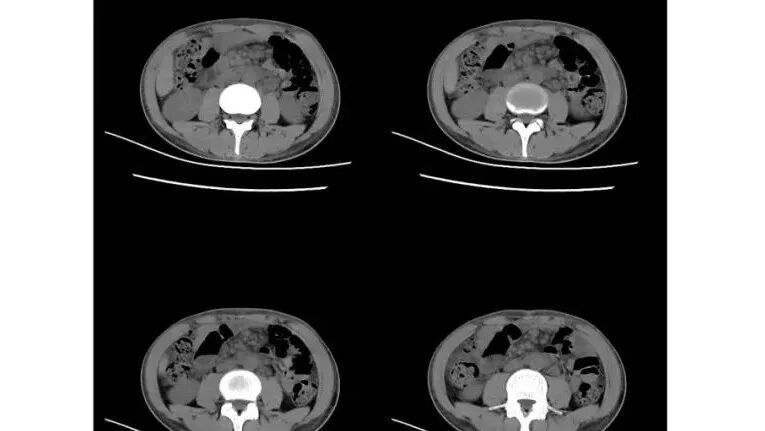

以下为2021-7-15日上腹部CT

影像与临床:1.青年男性,HlV阳性,颜面部皮疹(未提供皮疹图像)、发热(高热),实验室CRP、PCT高,T-Spot阴性。2.右肺下叶空洞结节,壁厚不均,边界清楚,其内线状影,未见液平及钙化,未见卫星灶,纵隔淋巴结增大,双侧腋窝见增大淋巴结。心腔内低密度提示贫血可能。肝脾影增大,未见结节影及块影。腹膜后见多发增大淋巴结。